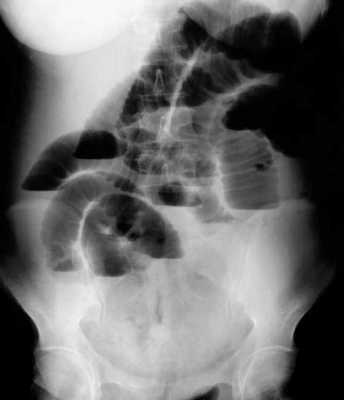

(г, д) На рентгенограммах выявлен симптом «штопора» — спиральная конфигурация 4-го отдела двенадцатиперстной кишки и проксимальной части тощей кишки.

б) Лучевая диагностика заворота тонкой кишки. При стандартной рентгенографии чаще выявляют неспецифические признаки, и она редко бывает информативной в диагностике. Симптом «штопора», известный как диагностический признак заворота средней кишки, отображает спиральную конфигурацию 4-го сегмента двенадцатиперстной кишки и проксимальной части тощей кишки, классически выявляемую при рентгенографии у детей, особенно у младенцев. Его можно визуализировать в переднезадней и боковой проекциях.

2. При завороте средней кишки определяют характерные признаки, такие как симптом «штопора» (спиральная конфигурация дистальной части двенадцатиперстной кишки и проксимальной части тощей кишки), выявляемый при рентгенографии, и симптом «водоворота» — перекручивание верхней брыжеечной вены, брыжеечного жира и кишки вокруг верхней брыжеечной артерии, выявляемый при КТ с контрастированием.